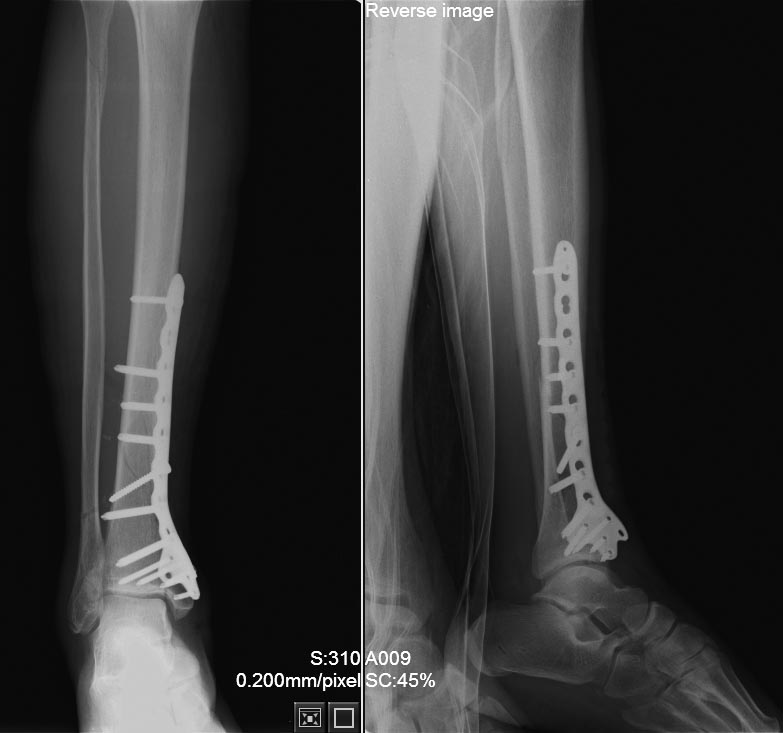

[Ortho] Перелом нижней трети голени - стержень или пластина?

Привожу снимки после операции